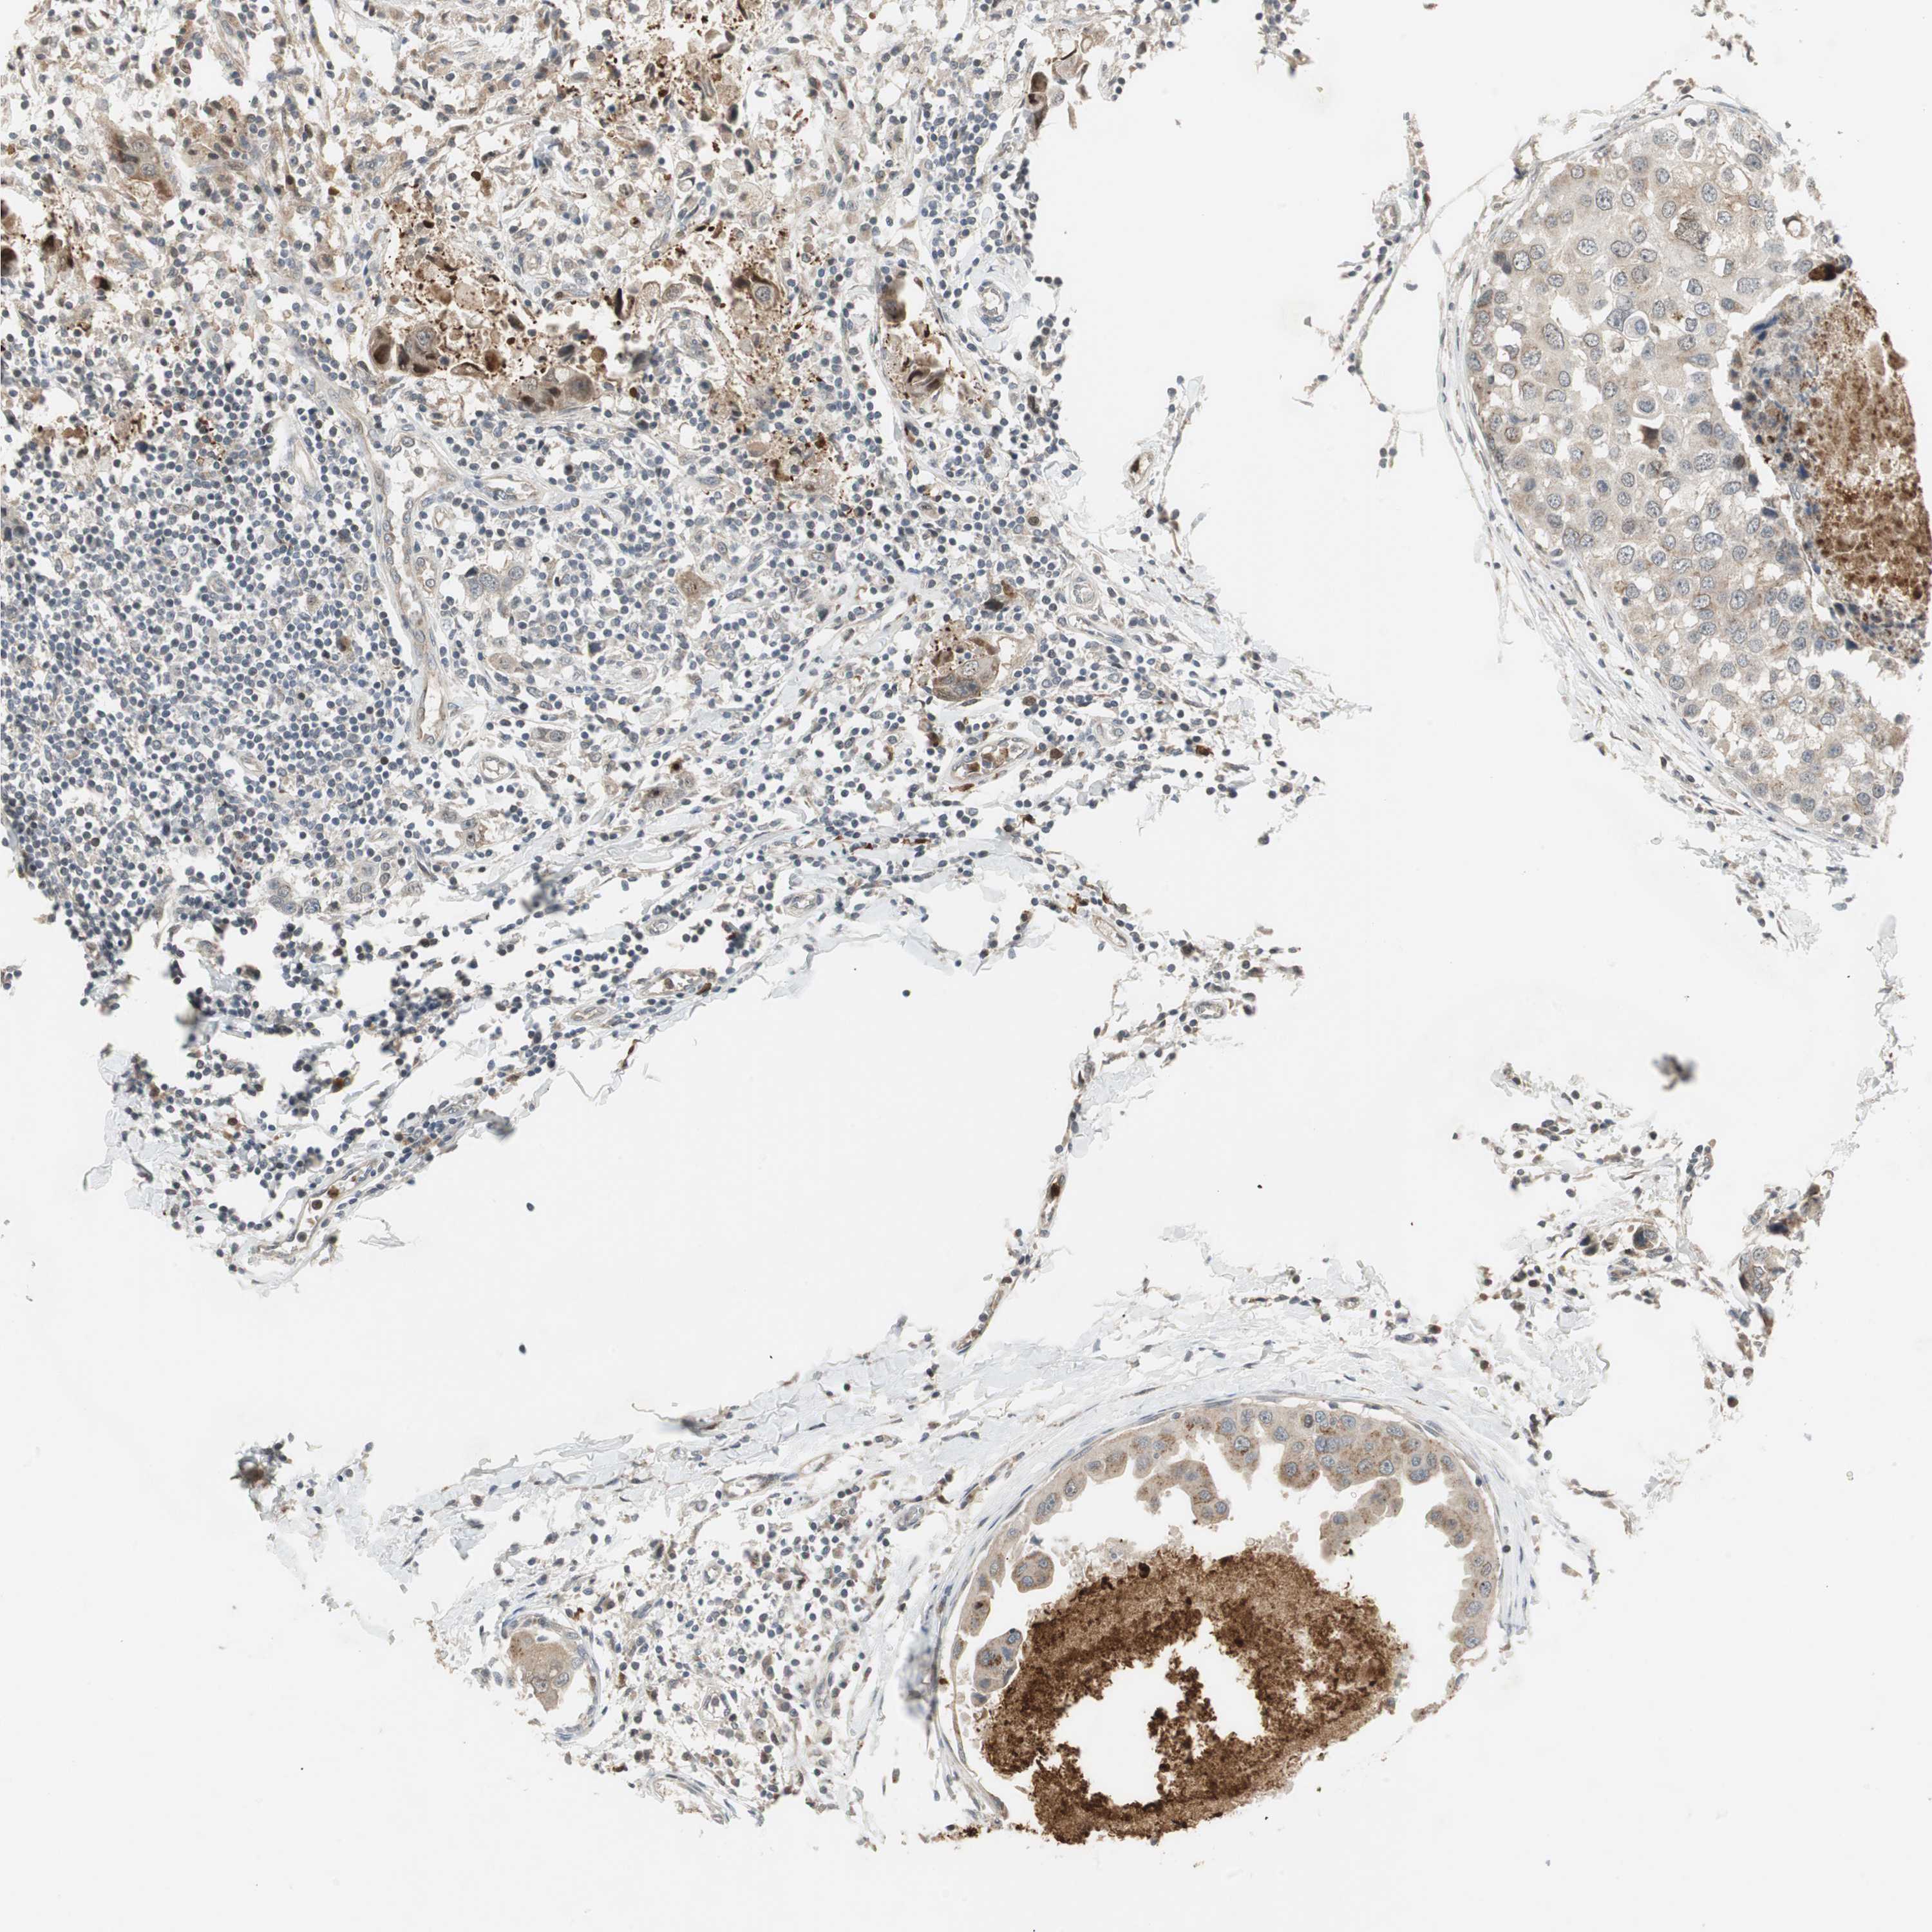

CANCER BREAST CANCER Show tissue menu

BRCA TCGA BRCA VALIDATION PROTEIN EXPRESSION